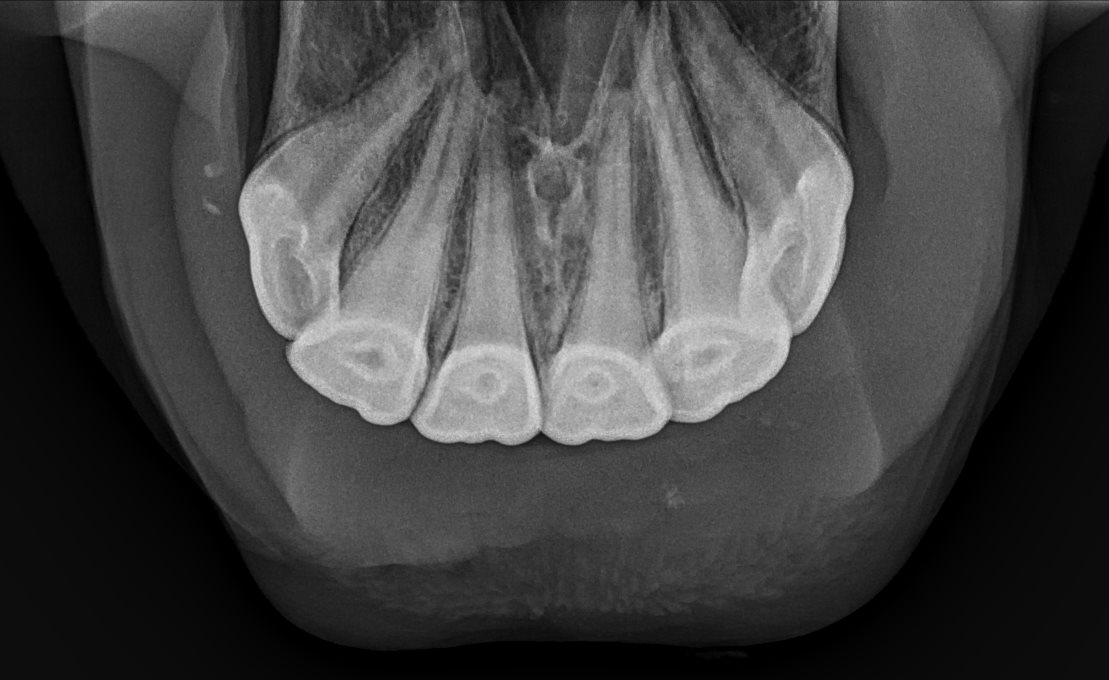

X-ray of normal incisors in a mare in her upper teens.  Note the tapered, well defined roots